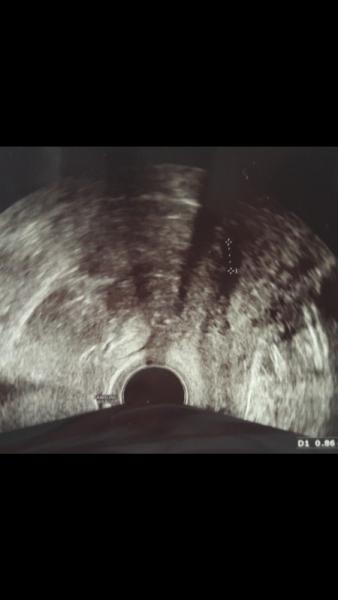

Hatte heute meinen ersten Termin beim Frauenarzt. Bin in der 4ssw .Alles ist Zeitgerecht und die Gebährmutterschleimhaut gut hoch aufgebaut. Jetzt Schritt für Schritt Woche für Woche hoffen das alles gut geht. Lg Biene

Bild zu War heute beim ersten Baby TV - Kinderwunschbehandlung